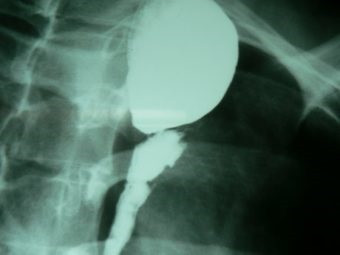

Dilatación esofágica con balón

Envíado por Dr. Carlos Miguel Zavaleta Consuegra